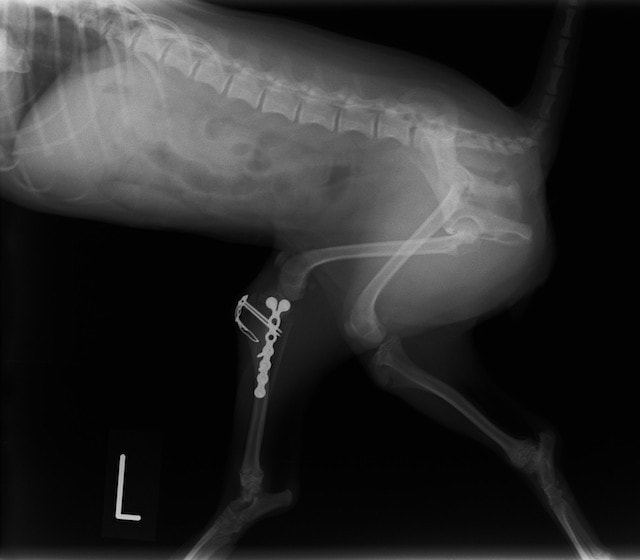

症例:交通事故による椎体脱臼

柴犬:9歳、避妊雌

交通事故直後、胸腰部に激しい疼痛、両後肢に完全麻痺を認め、シェフシェリントン徴候を呈していました。レントゲン検査において、第11-12胸椎間の脱臼が認められました。

脊髄の減圧、脊柱管の再構築・安定化を目的に、片側椎弓切除術およびMatrixMANDIBLE Plateによる椎体固定を実施しました。

隣接椎体を架橋するようにプレートを設置しました。

術後レントゲン写真